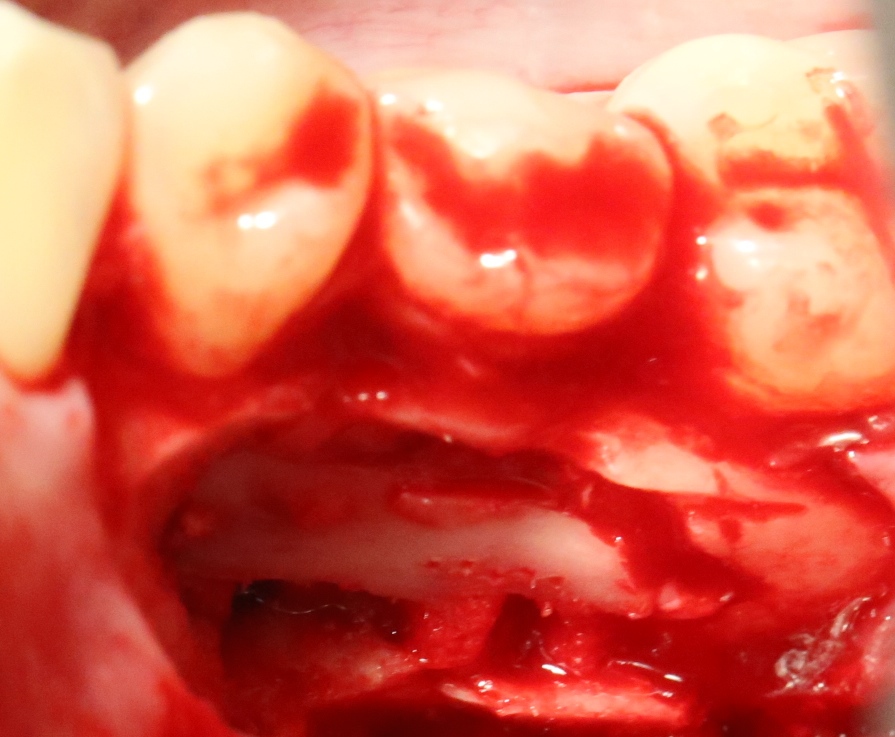

Однако, наши сверхкомплектные зубы вываливаться не хотят. Потому что их коронки образуют что-то вроде клина, который непросто вытащить через маленькое трепанационное отверстие.

Поэтому мы, всё также, с помощью ультразвука, отпиливаем коронку одного из зубов:

После чего, зубы вываливаются из лунок самостоятельно. В прямом смысле слова: